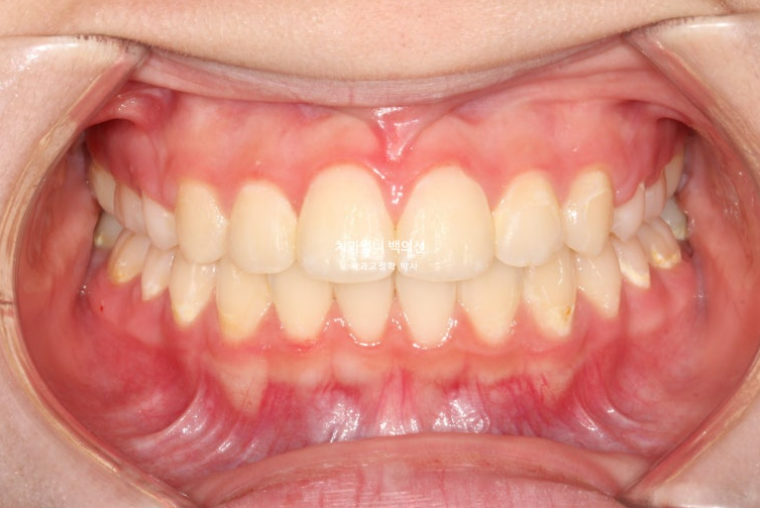

중심선은 잘 맞습니다.

유난히 커보이던 앞니는 돌출이 해소되고 가지런해지면서 누명을 벗었습니다.

교합은 좋습니다.

간혹 작은어금니 발치교정은 4개를 빼야 교합이 맞지 않나에 대한 질문을 듣는데 위에만 돌출인 경우 위에만 2개 빼는 교정도 좋은교합으로 마무리 되는 교정이랍니다.

발치교정으로 앞니 돌출이 해소가 되어 예쁜 입매가 되었으며 이제야 비로소 입이 편하게 다물립니다.

돌출입이 해소가 되며 입매가 예뻐졌습니다.

돌출입으로 발치교정을 고민중인 분들에게 도움이되셨기를 바랍니다.